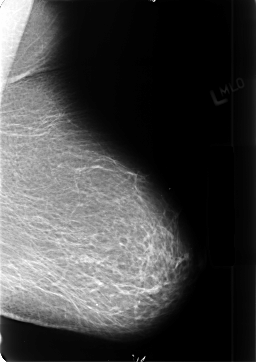

B_3402_1.LEFT_MLO

B_3402_1.LEFT_CC

LEFT_MLO LINES 4704 PIXELS_PER_LINE 3320 BITS_PER_PIXEL 12 RESOLUTION 50 NON_OVERLAY